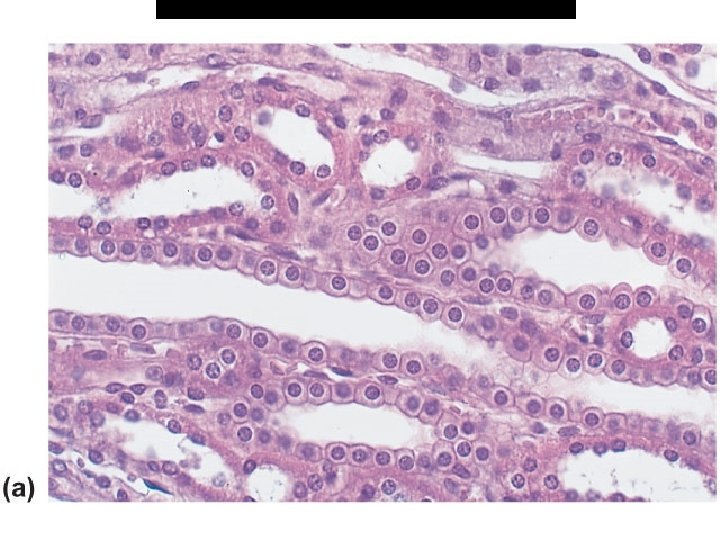

1. simple cuboidal epithelium * F – secretion, absorption * L – kidney tubules, ducts of glands, ovaries

B. Cuboidal Epithelium